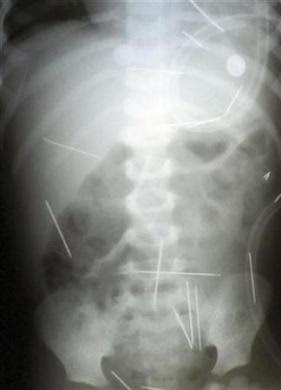

This x-ray of a young boy (2 1/2 years old) in Brazil shows (31) sewing needles that have been stuck in his body. Not just stuck in a little ways but inserted into his lungs, heart, liver, neck all over his body! This was done by his stepfather and a new girlfriend. His stepfather is 30-year-old Roberto Carlos Magalhaes and has been arrested and confessed to putting the needles in the boy’s body at the behest of his lover who said the act would help the two to stay together and enact revenge on his past wife. He also said that over a one month period the needles were put into the child body.